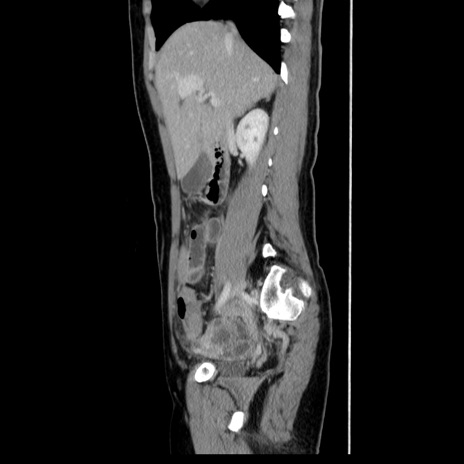

CT